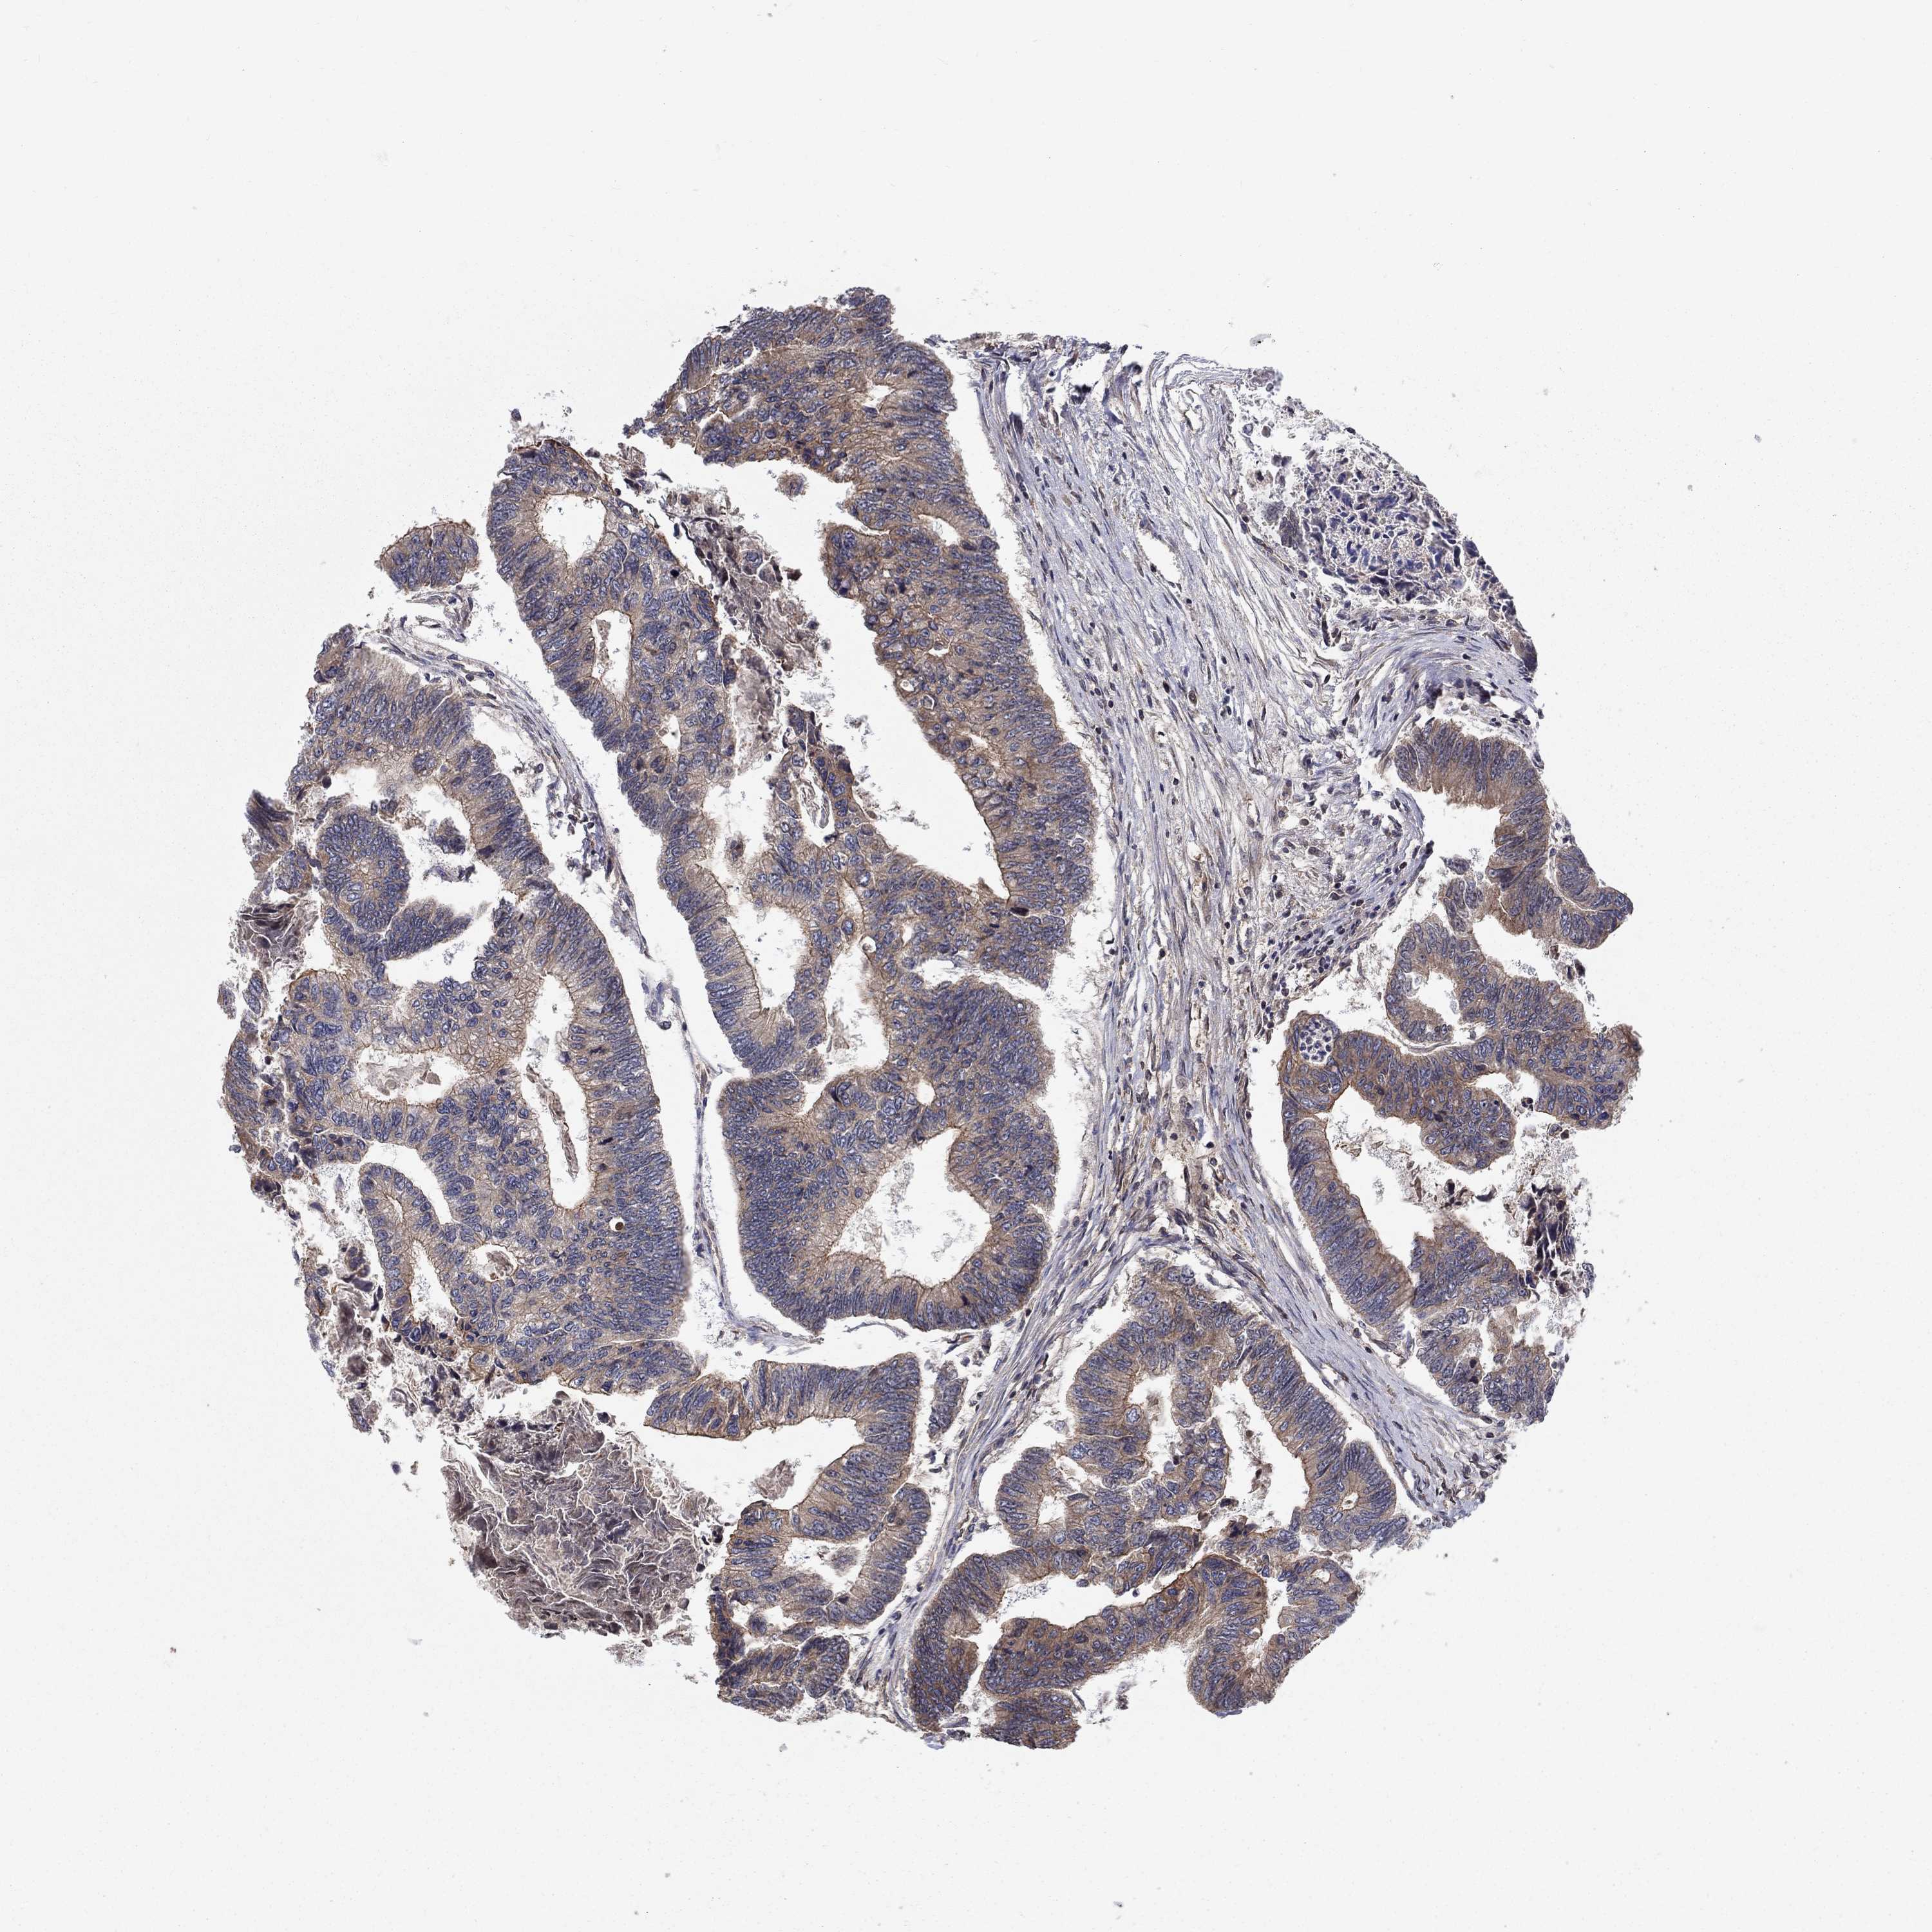

Colorectal cancer

Human cancer

Colon adenocarcinoma